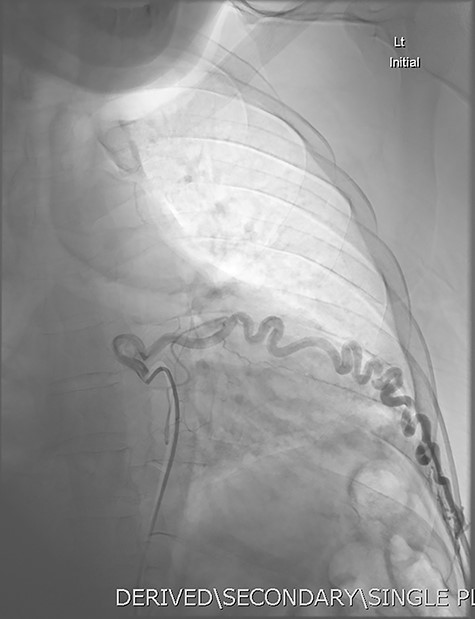

DSA utilizing superselective catheterization to demonstrate contribution to the PAVM via one of the many tortuous intercostal arteries.

Given the findings, he was referred to Interventional Radiology for a formal digital subtraction angiogram with view of transcatheter embolization. Under local anaesthetic and sedation, a 5-french sheath was placed in the left common femoral artery. Using a 5-french pigtail catheter, aortic angiography was undertaken, confirming the CTPA findings and demonstrating predominant supply of the vascular malformation via the left intercostal arteries and the left inferior phrenic artery (Fig. 4)—draining into the left inferior pulmonary artery and vein. Superselective catheterization of the left intercostal arteries (Fig. 5) and the left inferior phrenic artery (Fig. 6) are shown. Unfortunately, due to the malformation’s volume and complexity, embolization was abandoned. He was subsequently referred to Cardiothoracic Surgery, currently awaiting consideration and workup for ligation and resection via video-assisted thoracoscopy, and potentially thoracotomy.